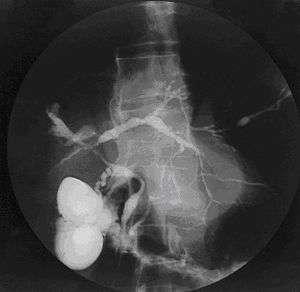

| Cholangiogram of primary sclerosing cholangitis. | |

Historically, a cholangiogram would be obtained via endoscopic retrograde cholangiopancreatography (ERCP), which typically reveals "beading" (alternating strictures and dilation) of the bile ducts inside and/or outside the liver. Currently, the preferred option for diagnostic cholangiography, given its non-invasive yet highly accurate nature, is magnetic resonance cholangiopancreatography (MRCP), a magnetic resonance imaging technique. MRCP has unique strengths, including high spatial resolution, and can even be used to visualize the biliary tract of small animal models of PSC.[16]